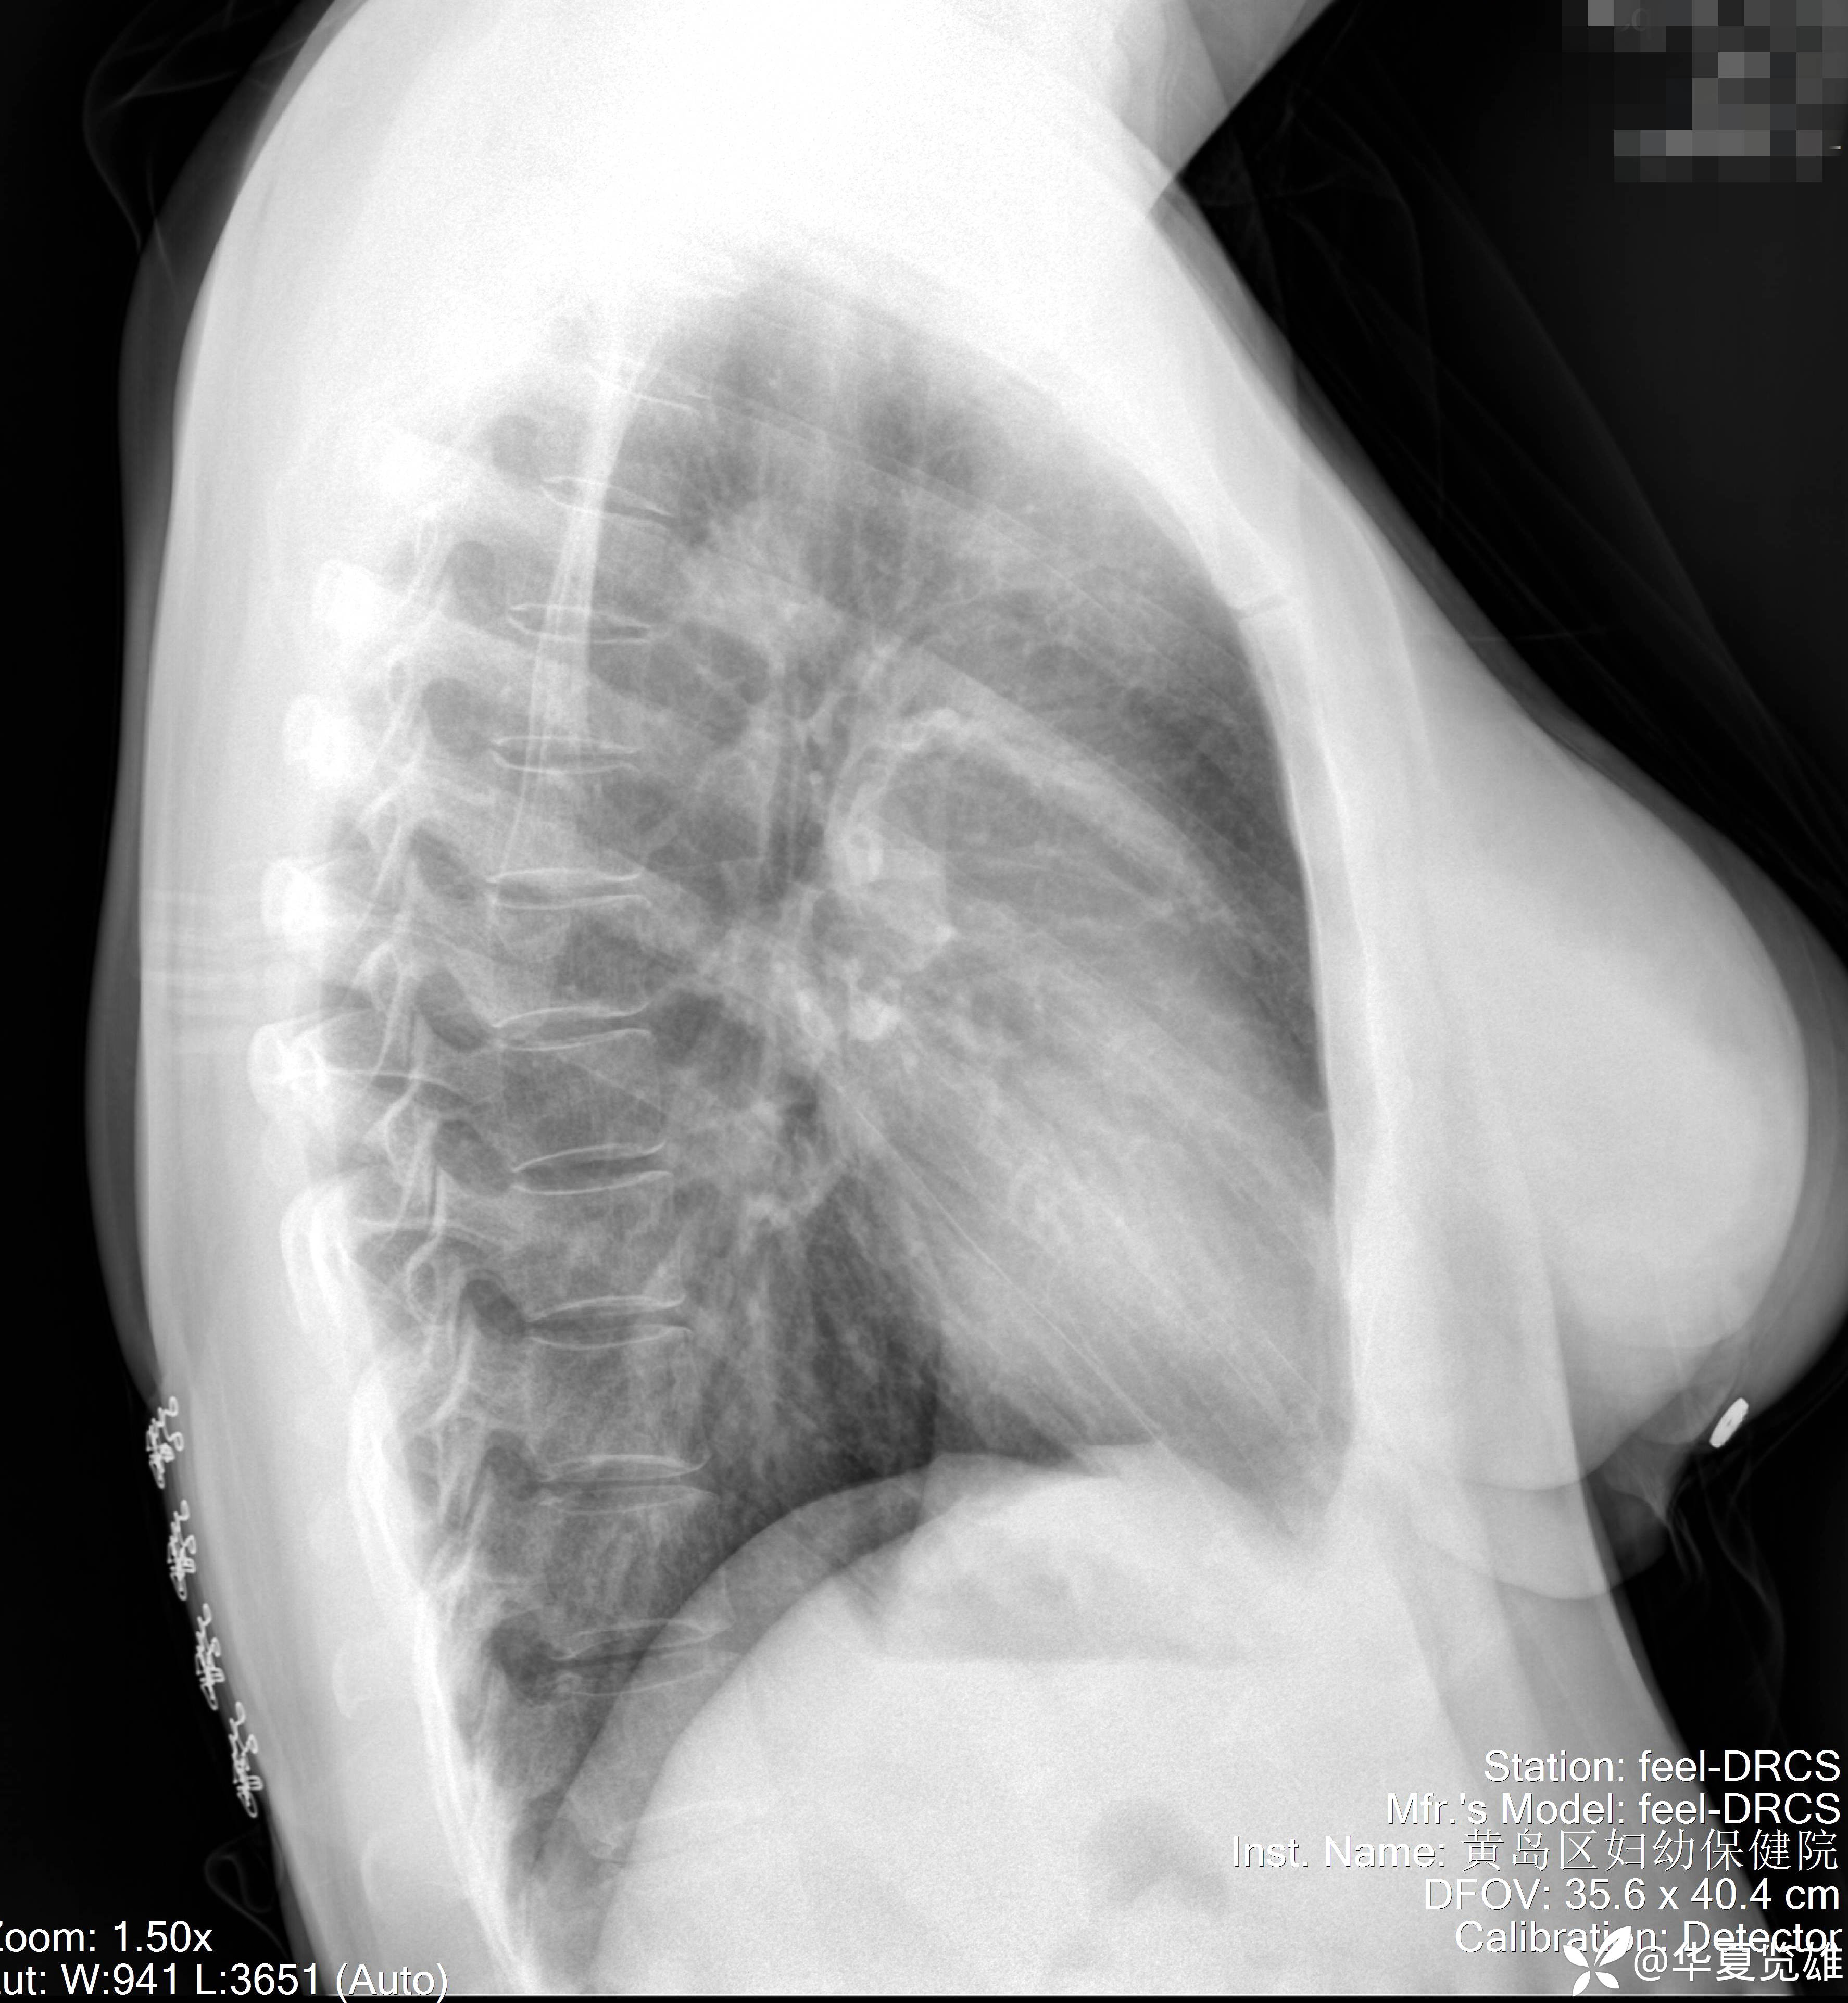

平片与CT:有无异常?公说公有理,婆说婆有理,到底谁在理,还得看CT.

患者性别:女

患者年龄:41岁

主诉及简要病史:人工流产前查体。

体格检查:无异常。

辅助检查:无异常。

1. 本例有无异常?

2. 住院患者入院前后,是选择胸片还是做胸部CT为好?